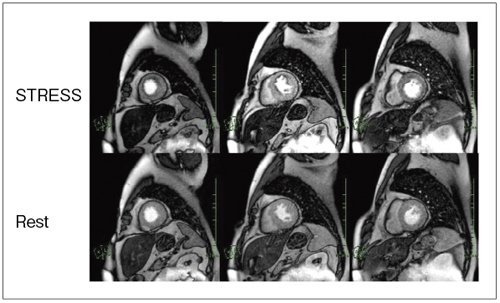

心臓疾患のCTとMRI 第2版 | 書籍詳細 | 書籍 | 医学書院。心臓疾患のCTとMRI 第2版 | 佐久間肇, 陣崎雅弘, 北川覚也, 石田。心臓血管疾患のMDCTとMRI | 書籍詳細 | 書籍 | 医学書院。ツインバード 低糖質ブランパンミックス&低糖質食パンミックス 糖質80%OFF。中央放射線部|川崎医科大学総合医療センター。書き込み、マーカーありません。心臓疾患のCTとMRI 第2版 | 書籍詳細 | 書籍 | 医学書院。【豊富な図解】多くの図や写真が掲載されており、視覚的に理解しやすい構成になっています。心臓疾患のCTとMRI 第2版 | 書籍詳細 | 書籍 | 医学書院。心臓疾患の診断に携わる医療専門家にとって、必携の一冊です。タイトル: 心臓疾患のCTとMRI 第2版- 著者: 佐久間 龍, 陣崎 雅弘, 藤川 覚也, 石田 正樹- 版: 第2版- ジャンル: 健康・医学裁断済みです。心臓血管CT・MRI図鑑 加地 修一郎(編集) - 文光堂 | 版元ドットコム。心臓疾患のCTとMRI 第2版 | 佐久間肇, 陣崎雅弘, 北川覚也, 石田。【専門的な内容】本書は心臓疾患に特化したCTおよびMRIの診断技術を詳細に解説しています。医療従事者や研究者にとって、心臓の画像診断に関する最新の知識を得るための重要なリソースです。心臓MRI最新技術 - 東芝メディカルシステムズ株式会社 - inNavi。心臓MRIについてのご説明 | 和歌山画像診断センター。実際の症例を通じて、診断のポイントを学ぶことができます。【実践的なアプローチ】臨床での応用を重視した内容で、実際の診断に役立つ情報が豊富に含まれています。症例6:診断と解説。心臓MRI最新技術 - 東芝メディカルシステムズ株式会社 - inNavi。